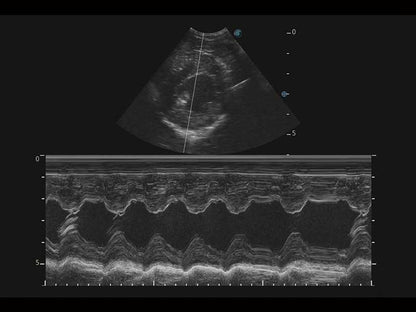

Az X Series Vet platform egy laptop kialakítású színes Doppler ultrahangrendszer, amely kiemelkedő képalkotó technológiáival van felszerelve, és professzionális állatorvosi szoftvereket kínál a kis kedvtelésből tartott állatoktól a nagy haszonállatokig. Kristálytiszta képalkotása és gördülékeny munkafolyamata új, továbbfejlesztett vizsgálati élményt biztosít, amely a magabiztos diagnózishoz szükséges pontosságot nyújtja.

Mivel az X Series Vet a SonoScape legújabb képalkotó technológiáit alkalmazza a nagy felbontású és mély penetrációjú képek előállításához, nagy mennyiségű diagnosztikai információ jeleníthető meg az ultrahang képernyőn. A továbbfejlesztett képminőség gyorsabb és pontosabb vizsgálatokat tesz lehetővé bármely állatfaj esetén.

A hatékonyságot, egyszerűséget és sokoldalúságot ötvözve az X Series Vet kiváló választás lógyógyászati vizsgálatokhoz. Speciális transzducerekkel és ló specifikus szoftverekkel felszerelve könnyedén készít lenyűgöző képeket az olyan alapvető alkalmazási területeken, mint az MSK, a reproduktív szervek vizsgálata, valamint a megfelelő penetrációt biztosítja hasi és kardiológiai vizsgálatokhoz is.